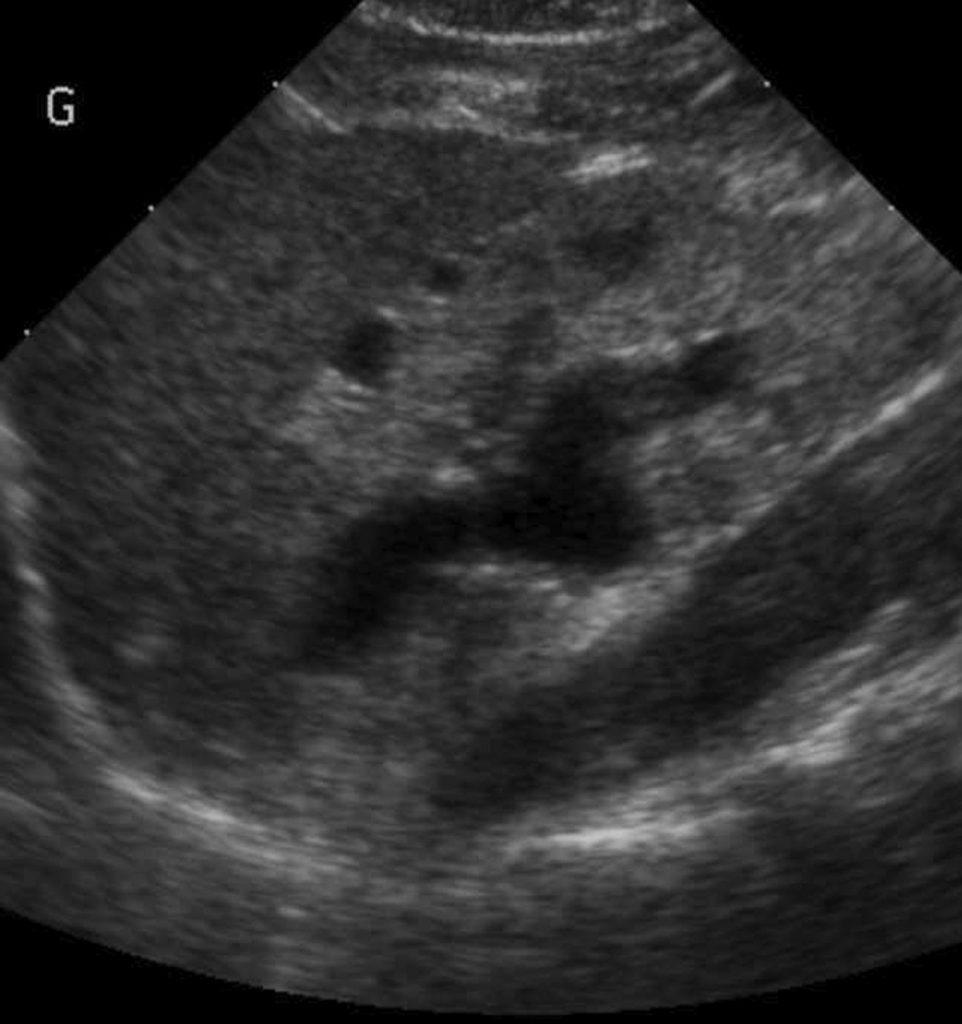

Fig. 107.2 Exemple de néphropathie de reflux.

Coupe échographique longitudinale. Le rein est plus échogène que la rate ; disparition de la différenciation corticomédullaire normale, kystes périphériques et dilatation pyélocalicielle.

Source : CERF, CNEBMN, 2022.